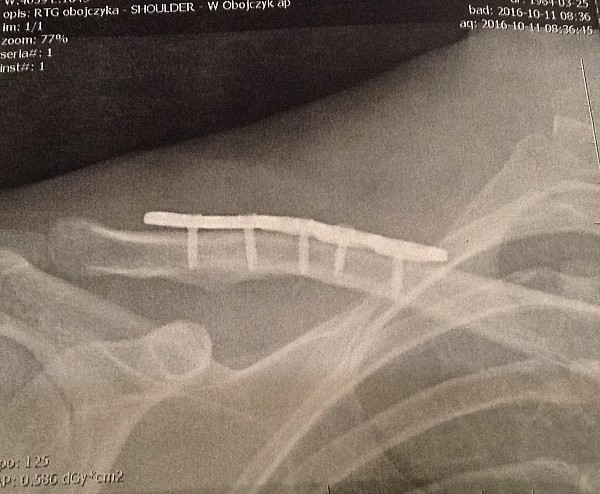

Kontuzja w świecie sportu wywołuje wiele negatywnych emocji. Złość, bezradność, rozgoryczenie, rozpacz to tylko niektóre z towarzyszących sportowcom odczuć. Nie pierwszy raz doświadczam podobnego stanu. Złamany obojczyk pokrzyżował moje plany w końcówce sezonu i pozbawił mnie długo oczekiwanego wyjazdu na Lazurowe Wybrzeże i startu w Roc d’Azur! Co więcej, uziemił mnie na dobre kilka tygodni, których operacyjnie zespolona kość potrzebuje do pełnego zrostu.

Podczas kontuzji zmienia się diametralnie cel treningowy. Teraz jest nim powrót do pełnej sprawności. W przypadku złamania obojczyka, pierwsze kilka tygodni to głównie cierpliwe oczekiwanie na zrośnięcie kości. Możemy sobie pozwolić na ruch w ograniczonym zakresie kontuzjowanej ręki.